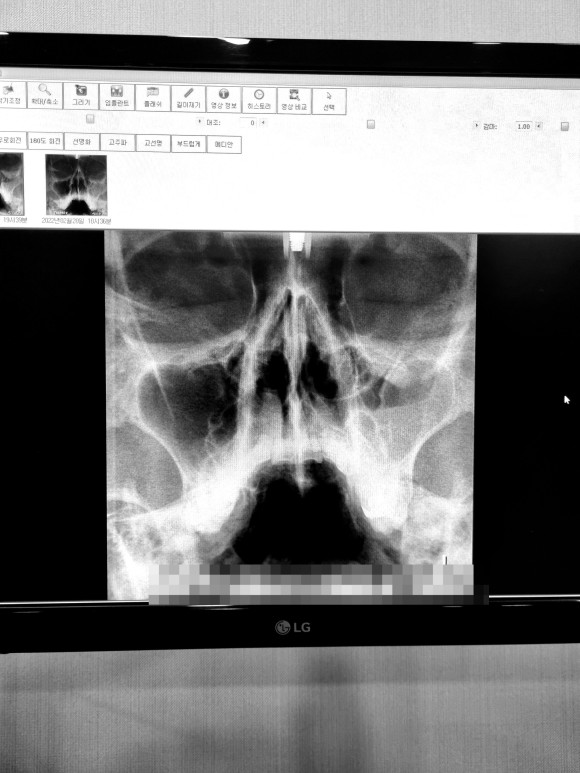

부비강염

사진은 좌우 반전되어 있고 사진의 오른쪽이 실제 얼굴상 왼쪽이다.)

좌우 차이가 보이나요?

시커멓게 비어 있는 것이 정상인데 반대편은 희고 뭔가 가득 차 있다

이 가운데 코뼈가 약간 구부러져 있다는 얘기도 들었다.생전에 몰랐던 것은 있지만 지장은 없다고 해서 그냥 살라고 했다.